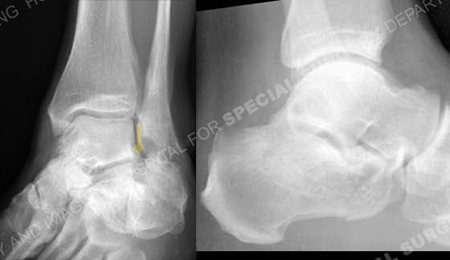

Injury radiographs revealing a calcaneus fracture with a depressed articular segment (arrow).